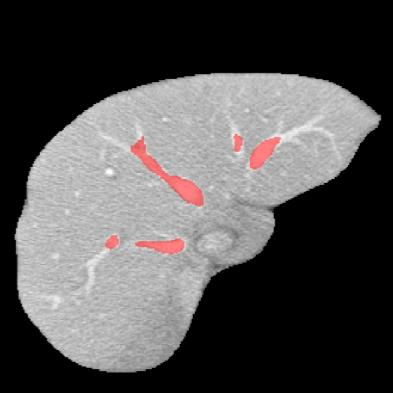

Manually segmenting the hepatic vessels from Computer Tomography (CT) is far more expertise-demanding and laborious than other structures due to the low-contrast and complex morphology of vessels, resulting in the extreme lack of high-quality labeled data. Without sufficient high-quality annotations, the usual data-driven learning-based approaches struggle with deficient training. On the other hand, directly introducing additional data with low-quality annotations may confuse the network, leading to undesirable performance degradation. To address this issue, we propose a novel mean-teacher-assisted confident learning framework to robustly exploit the noisy labeled data for the challenging hepatic vessel segmentation task. Specifically, with the adapted confident learning assisted by a third party, i.e., the weight-averaged teacher model, the noisy labels in the additional low-quality dataset can be transformed from "encumbrance" to "treasure" via progressive pixel-wise soft-correction, thus providing productive guidance. Extensive experiments using two public datasets demonstrate the superiority of the proposed framework as well as the effectiveness of each component.

翻译:将来自计算机地形学(CT)的肝脏船只人工分割,由于船只的低调和复杂形态,由于低调和复杂的形态,造成极端缺乏高质量的标签数据,因此比其他结构更需要专门知识和难度大得多。如果没有足够的高质量的说明,通常的数据驱动的基于学习的方法就会与不足的培训斗争。另一方面,直接引进低质量说明的额外数据可能会混淆网络,导致不良的性能退化。为了解决这一问题,我们提议建立一个新的、由教师协助的、有说服力的、有说服力的学习框架,为具有挑战性的肝脏船只分解任务强有力地利用响亮的标签数据。具体地说,在第三方(即加权平均教师模式)的协助下,经过变通的自信学习后,额外低质量数据集中的噪音标签可以从“阻力”转变为“压力”,通过渐进式的像素方法的软校正,从而提供富有成效的指导。使用两个公共数据集进行的广泛实验,显示了拟议框架的优越性以及每个组成部分的效能。